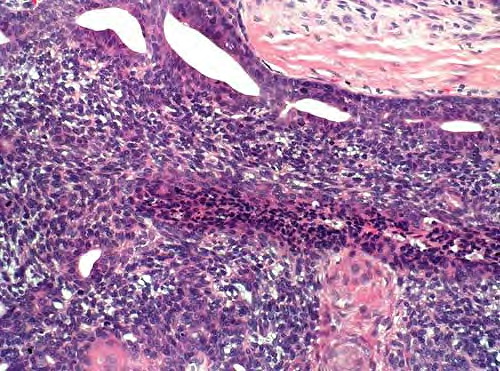

Diffuse large B-cell lymphoma = اللمفوما كبيرة الخلايا البائية المنتشرة